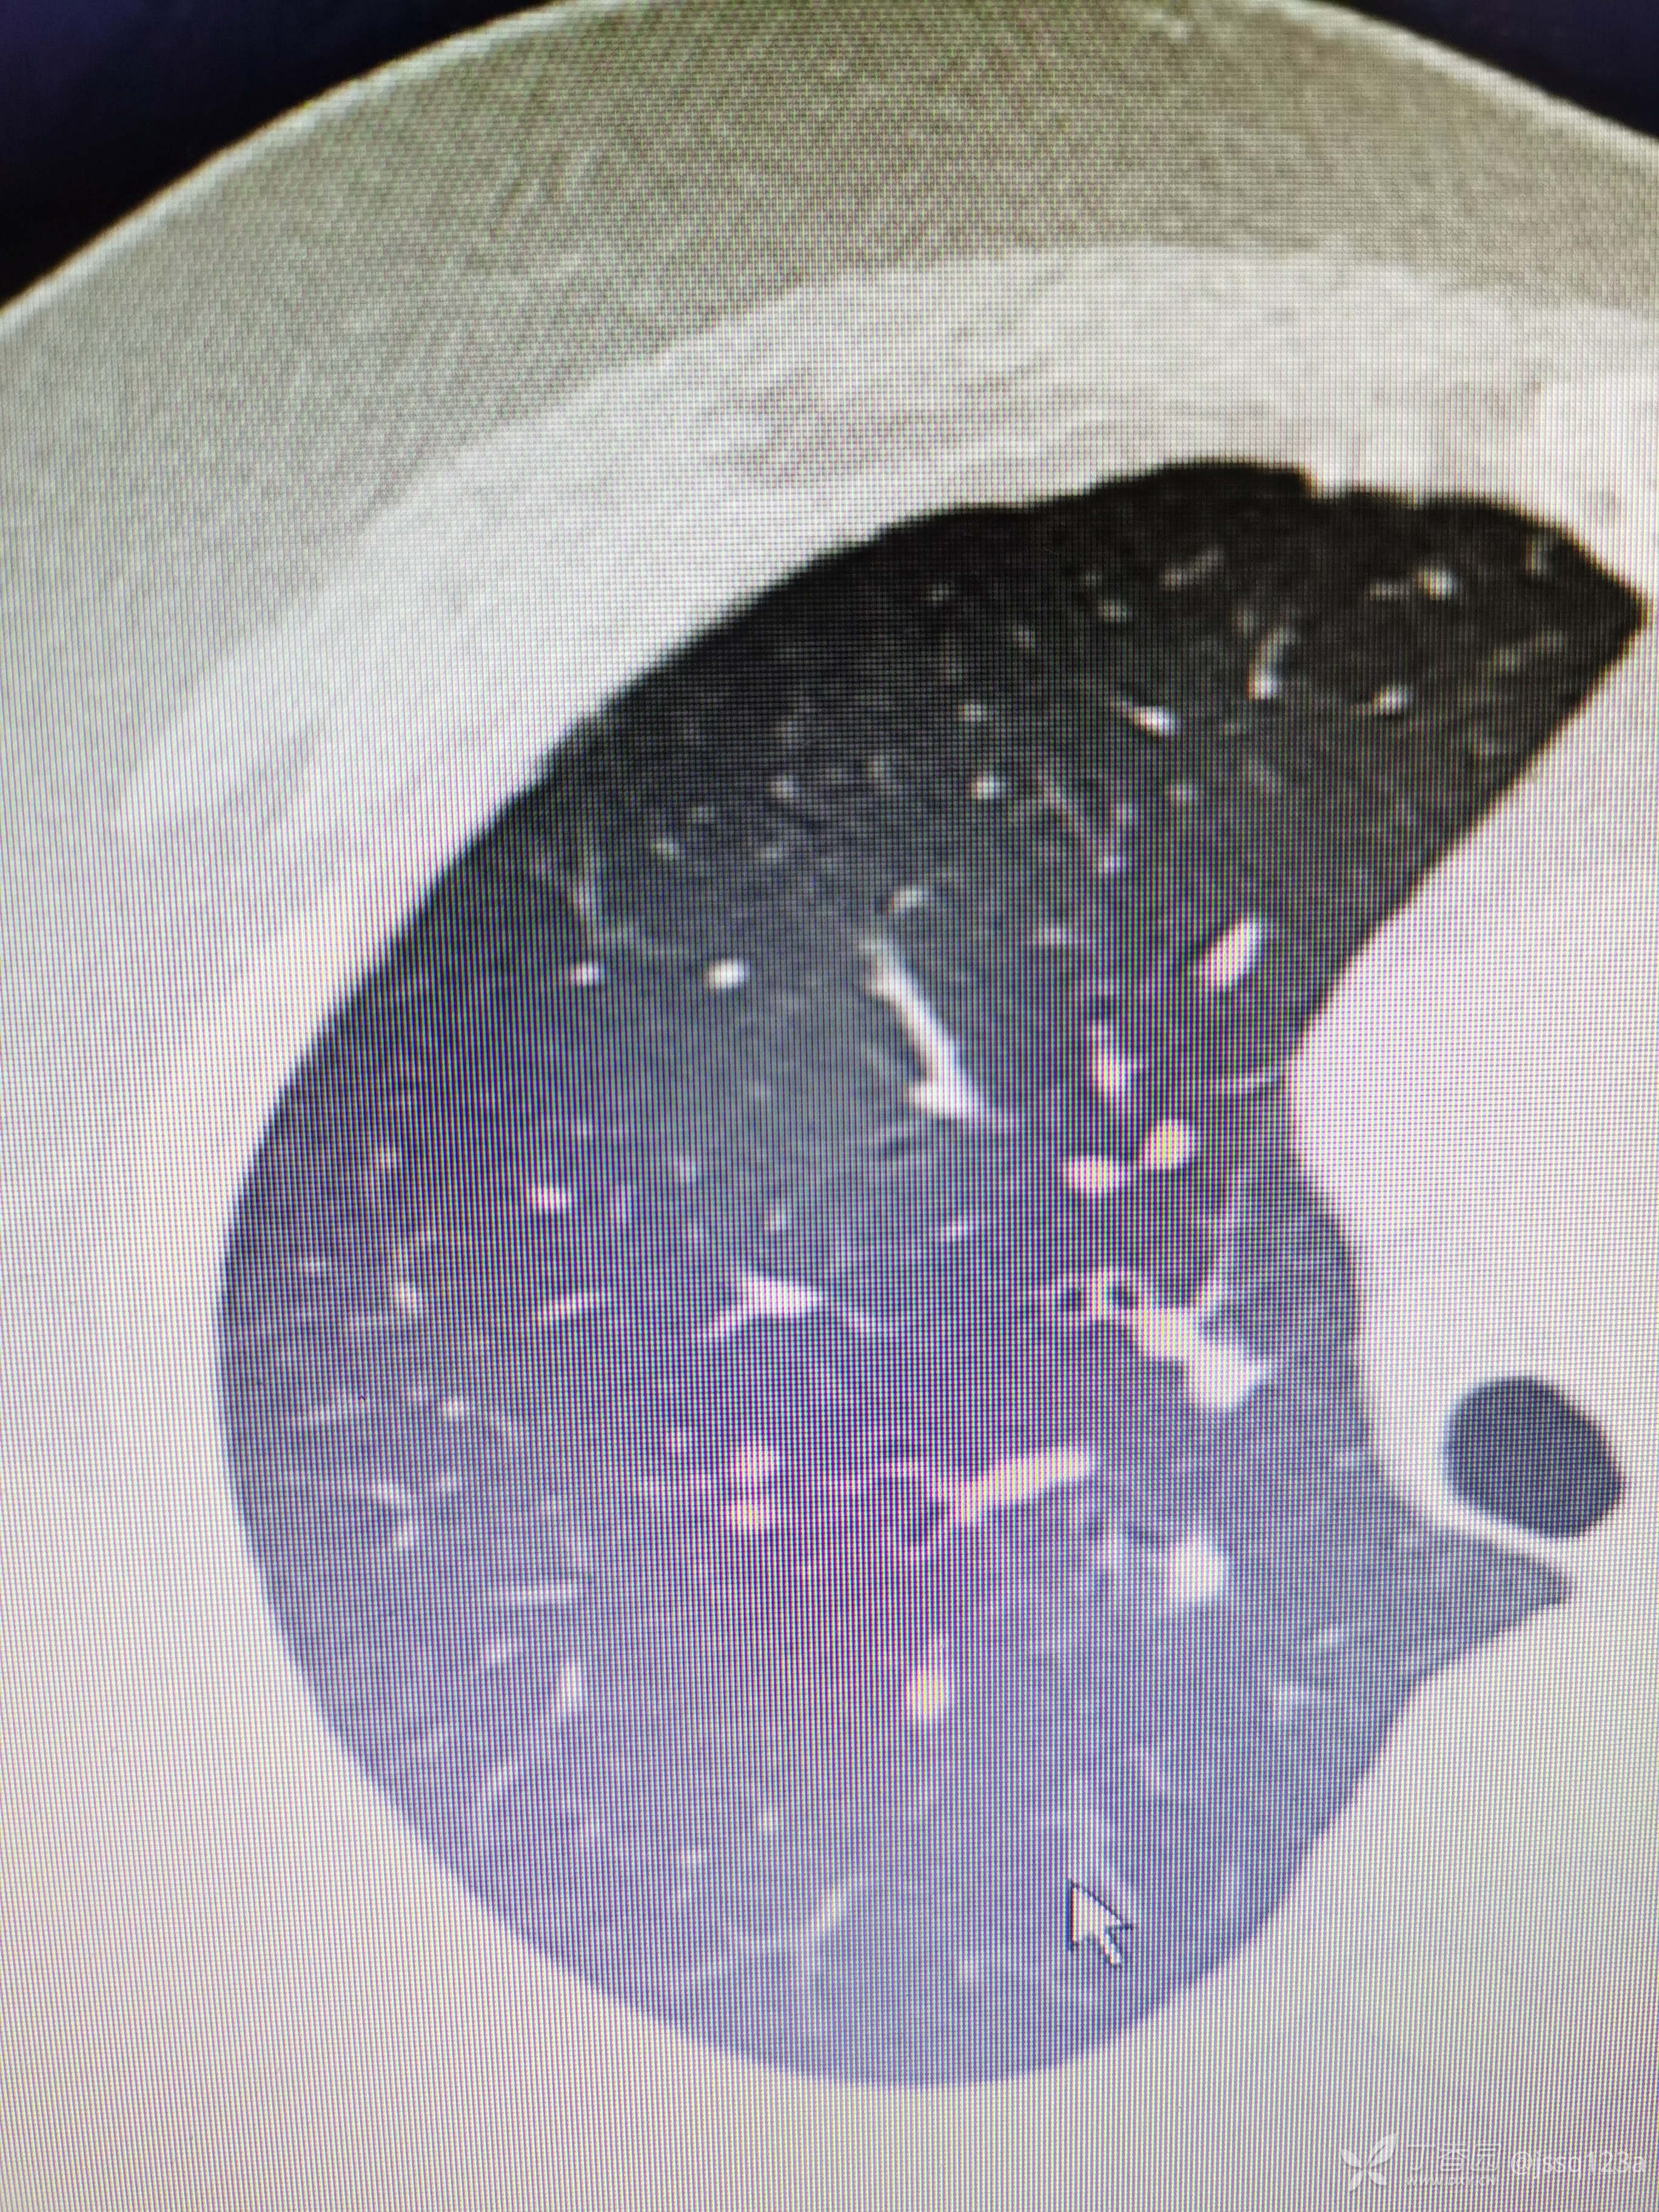

入院前胸部ct